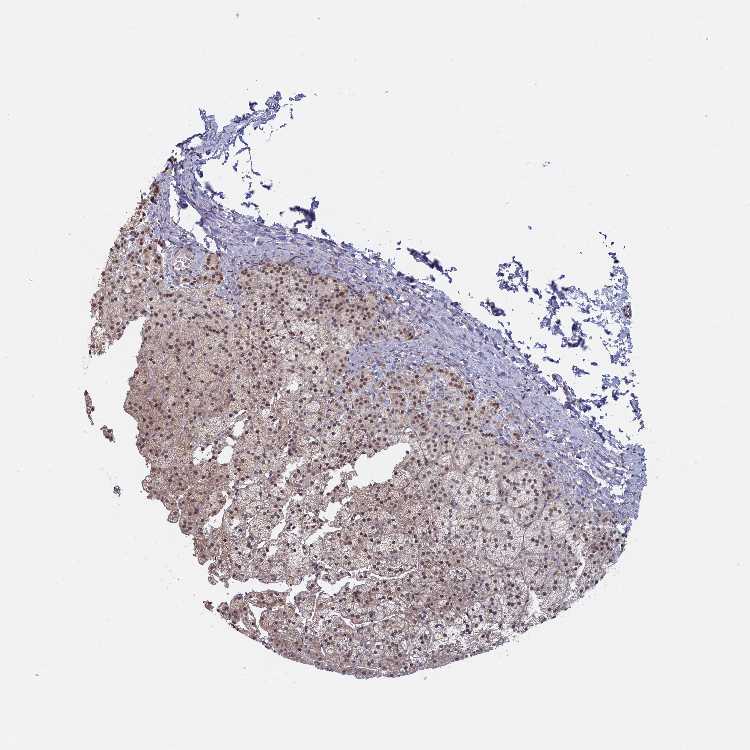

ADRENAL GLAND - Antibody stainingi

Antibody staining in the annotated cell types in the current human tissue is reported as not detected, low, medium, or high, based on conventional immunohistochemistry profiling in selected tissues. This score is based on the combination of the staining intensity and fraction of stained cells.

Each image is clickable and will lead to virtual microscopy that enables deeper exploration of all samples and also displays staining intensity scores, fraction scores and subcellular localization as well as patient and tissue information for each sample.

Antibody HPA040914Antibody HPA041187

Glandular cells LowLow